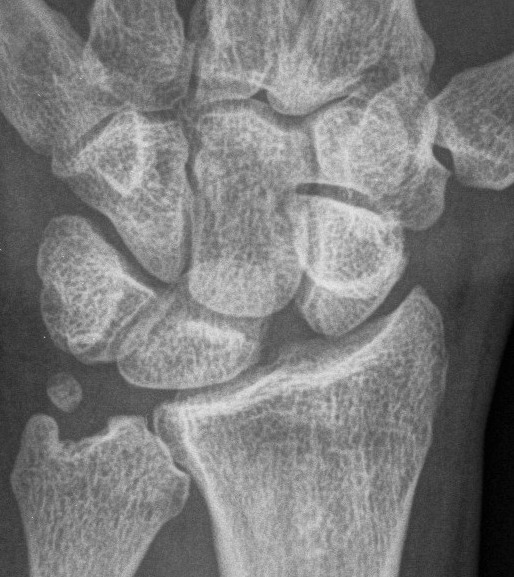

X-ray

Scapholunate gap > 3 mm

AP

| Terry Thomas sign | Cortical ring sign | Scaphoid shortened |

|---|---|---|

|

Increased scapholunate interval > 3 mm compared with other side |

End on view of distal scaphoid due to flexion | Shortened due to flexion |